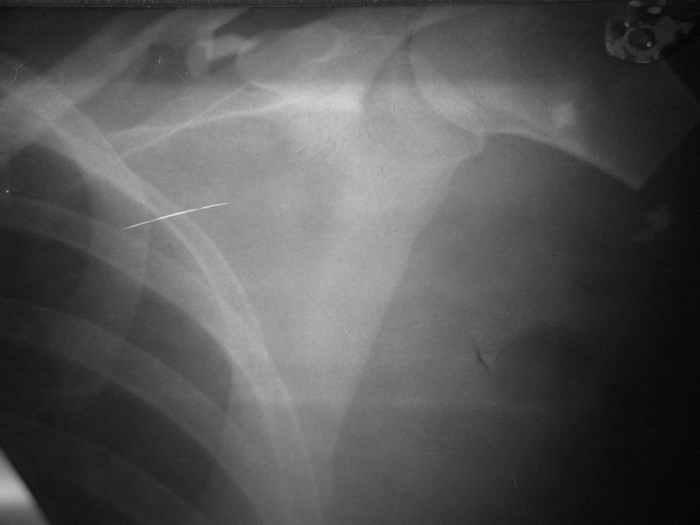

Убольной З. 26 лет, пострадавшей в результате ДТПимеетсз травматический отрыв левой верхней конечности на уровне проксимального отдела плечевой кости.В ургентном порздке (08.08.05) произведена ПХО раны с формированием культи конечности.В настозщее времз заживление полное.Имеютсз фантомные боли, приемущественно во вторрой половине днз.Фоторентгенограмма прилагаетсз.